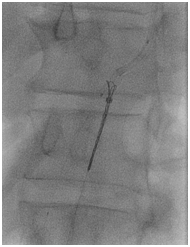

A 66-year old male with long standing history of type 2 diabetes, hypertension, dyslipidaemia and ischemic heart disease with prior history acute myocardial infarction treated with primary PCI to LAD with 3.0x22 mm drug eluting stent. Came for a staged PCI for a significant proximal RCA lesion. Following obtaining an informed consent and reload with 300 mg of Plavix. Right radial approach was selected patient received 7000 units of heparin. A 3DRCguidingcatheter was used to intubate the RCA following failure to engage with Judkin 4 guiding catheter, BMW wire advanced all the way to the distal end of RCA, lesion predilated by2.5x15mm compliant balloon to 12 atmospheres (Figure 1). A 3.5x 22mm Xience expedition stent was placed across the lesion under fluoroscopy. It was noted that the guide was not stable. It was decided to deploy the stent with the first fluoroscopy the stent appeared to have dislodged into the ascending aorta with the wire (Figure 2). Now the stent with an inflated balloon the guiding catheter and the wire all hanging in the ascending aorta. The initial decision to remedy this was to carefully and slowly withdraw the entire system along the course of the subclavian system and deploy the stent in a safe spot (Figure 3). But because of tortuosity it was thought to snare the entire system through a large femoral sheath. An 8 Fsheath was inserted into the right femoral artery and a 6 F ensnare system taken to the ascending aorta and grabbed the inflated balloon (Figure 4) and stent slowly moved down into the abdominal aorta under fluoroscopy. Then the balloon was deflated slowly and the snare tightened across the stent (Figure 5) and taken outside the body through the 8 F sheath (Figure 6) post snare femoral angiogram showed no injury to the femoral artery and a successful snaring of the dislodged stent. Patient was brought at alater date for a successful direct PCI to the RCA. This time the guide selected was an Amplatzer 0.75 (Figure 7).

Figure 1 Predilatation of the RCA lesion.